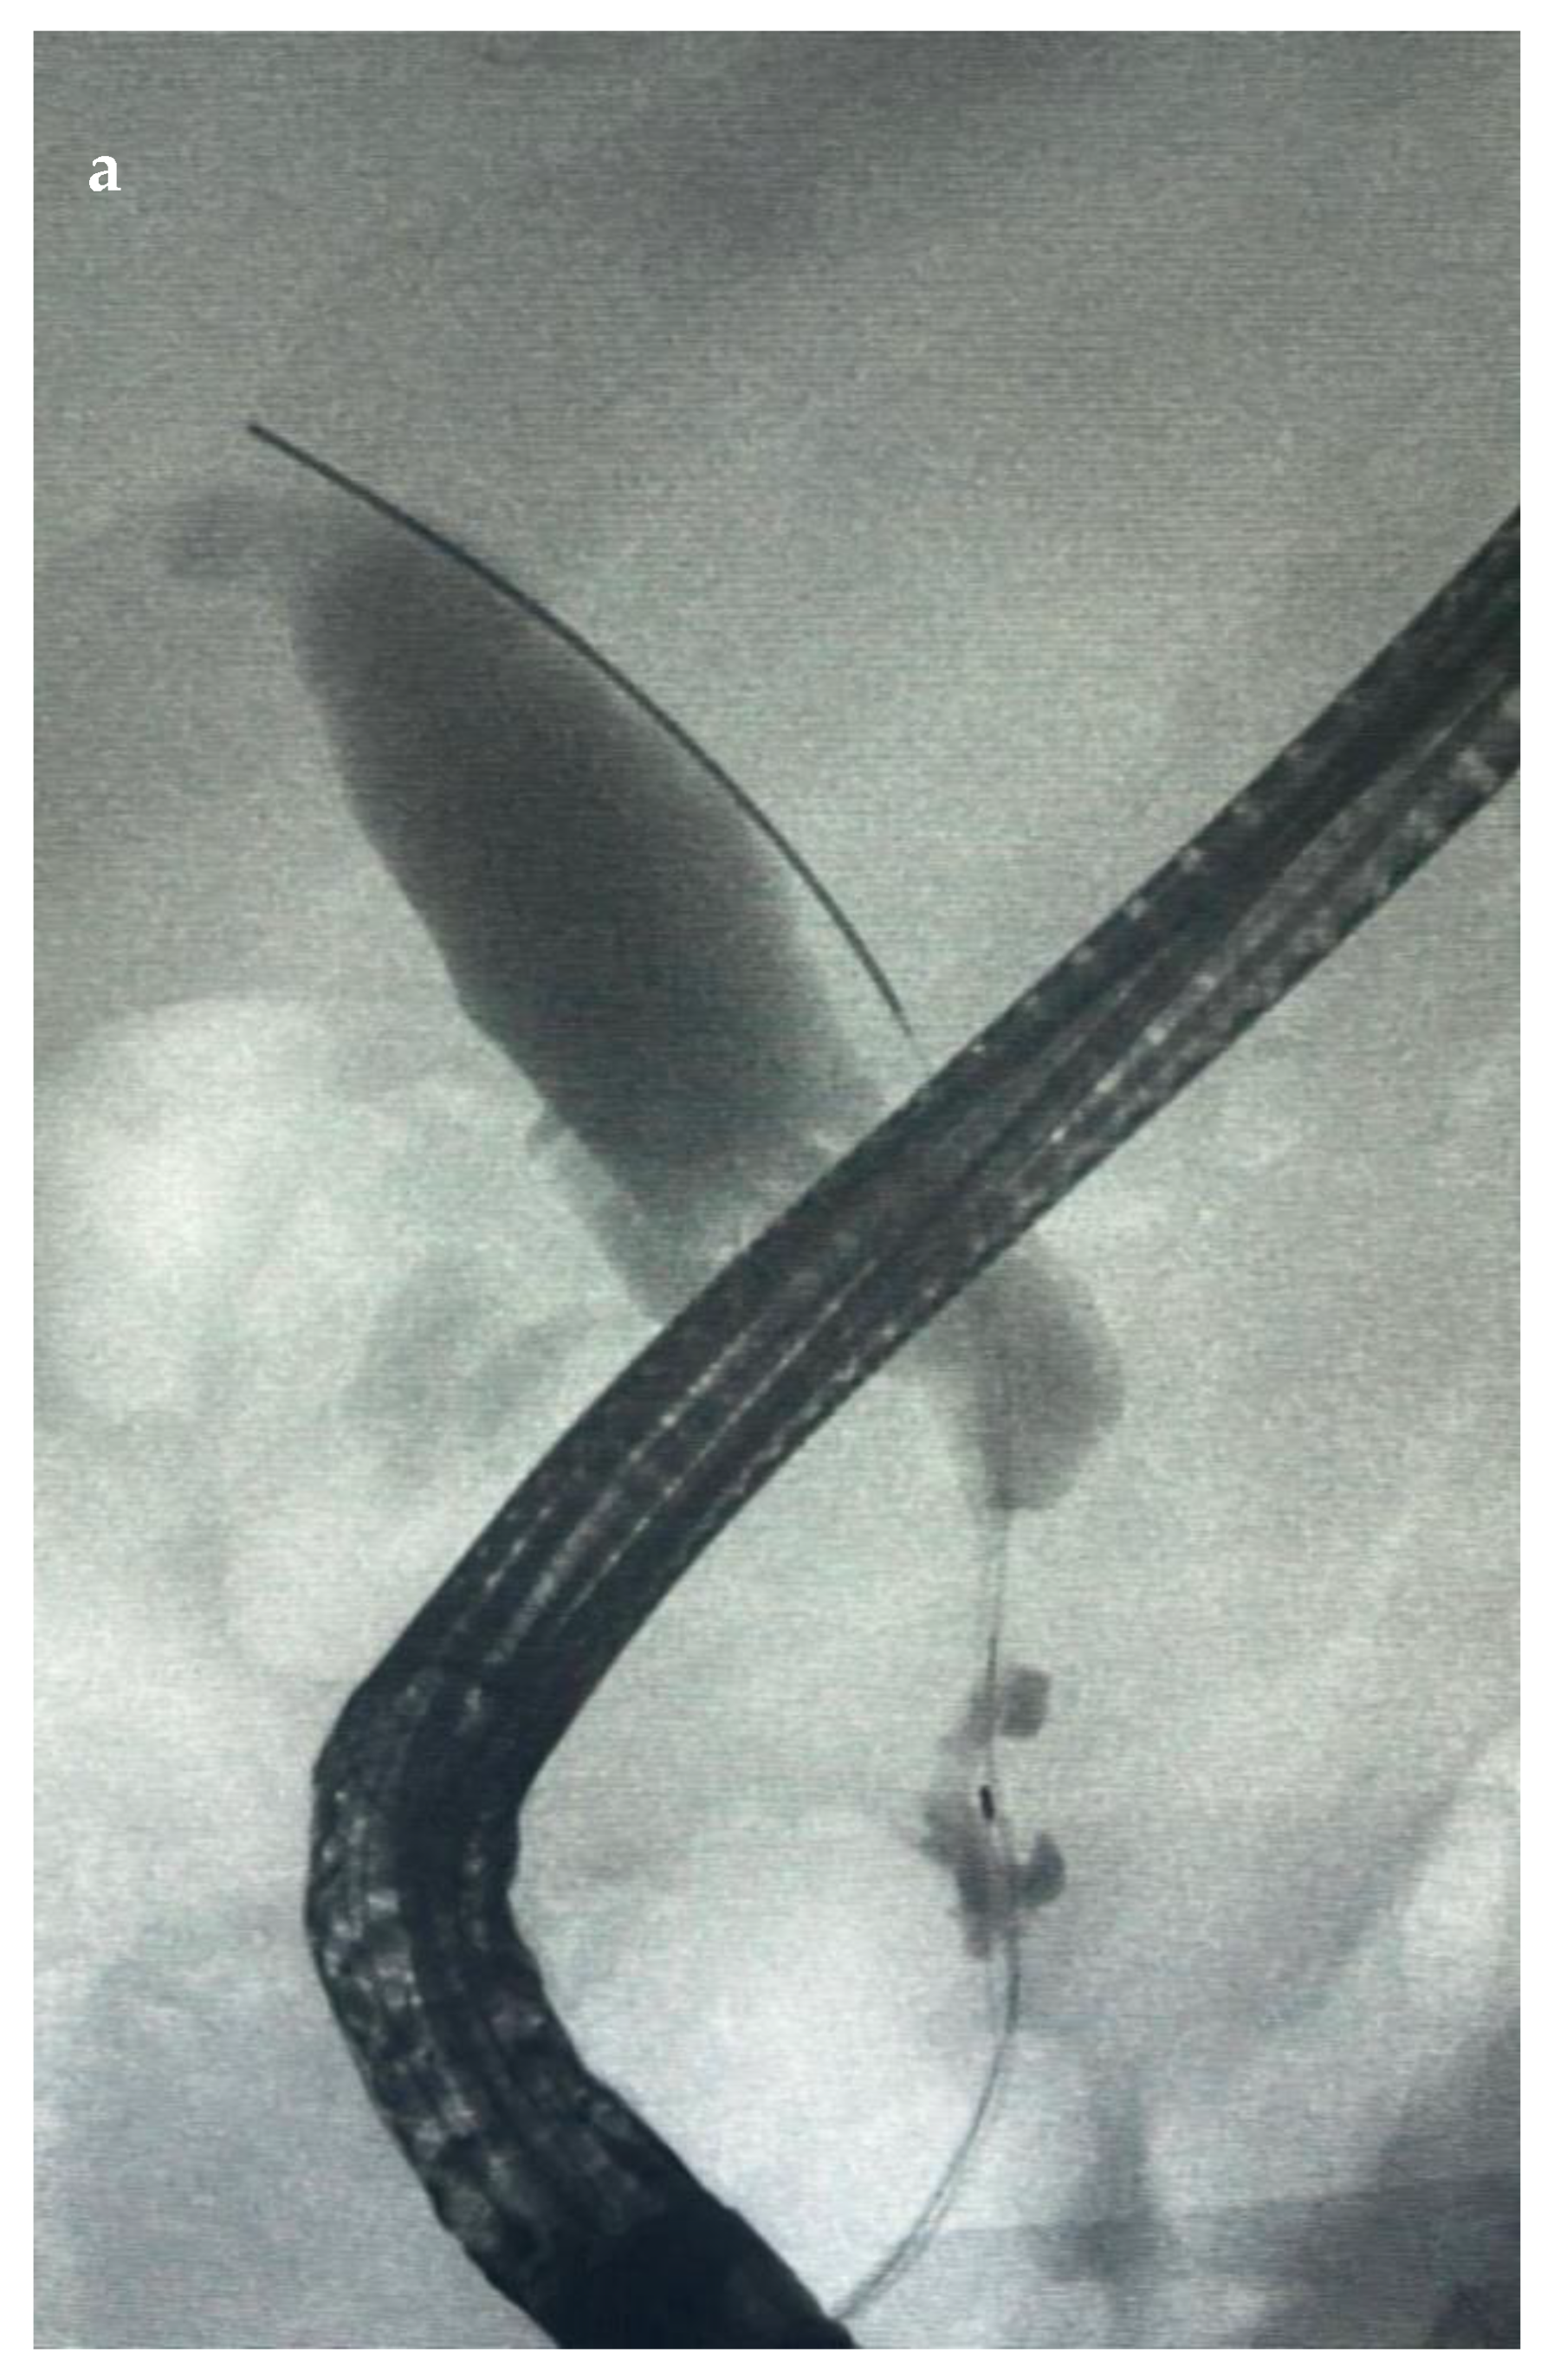

7.1.1. Endoscopic Biliary Stenting (EBS)

7.1.3. EUS-Guided Biliary Drainage (EUS-BD)